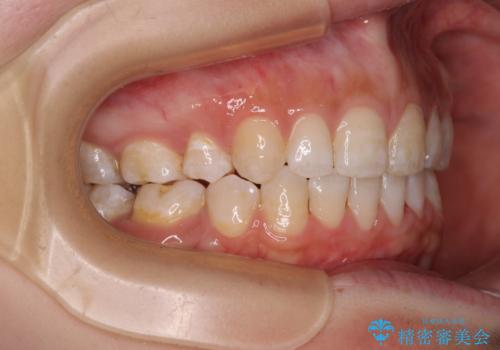

- 口元の突出感と上下前歯のズレを気にして来院された患者様です。

舌の突出癖により上下の前歯は非接触であり、更には奥歯の咬み合わせが非対称となっている状態でした。

通常は上下左右の第一小臼歯4本を抜歯することになりますが、右側臼歯部の咬合が上顎前突気味であったため、下顎右側のみ第二小臼歯を抜歯し、ワイヤー装置にて矯正治療を行うこととしました。

第二小臼歯抜歯はイレギュラーな治療手段であり、治療期間が延びる傾向にありますが、舌のトレーニングをしっかりと行ってくださり、2年弱という非常に短い期間で理想的な仕上がりを達成することができました。